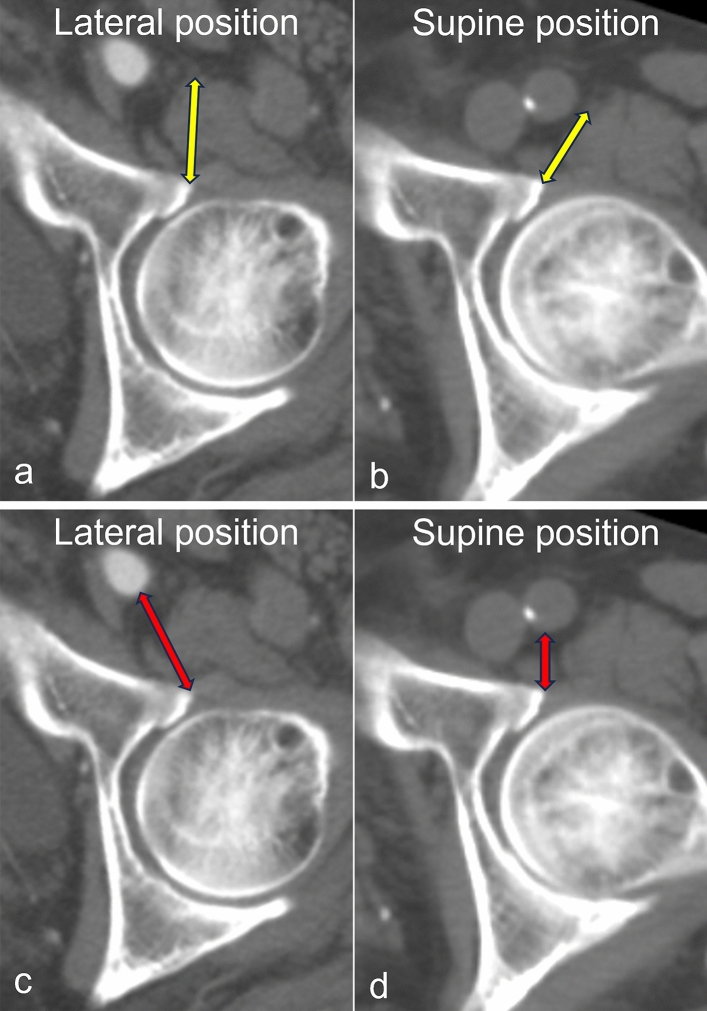

Materials and methods: This multicenter retrospective study included 111 patients who underwent lateral and supine computed tomography (CT) from 2016 to 2023. CT images were reconstructed in the anterior pelvic plane. The horizontal distance from the anterior margin of the acetabulum to the femoral nerve (Distance N) and femoral artery (Distance A) was measured. The difference in Distance N between the two positions (ΔLateral-supine Distance N) was calculated by subtracting the supine value from the lateral value.

Results: The average Distance N was 26.5 ± 5.1 mm in the lateral position and 21.1 ± 4.4 mm in the supine position, with the nerve located significantly closer to the acetabulum in the supine position (P < 0.001). Similarly, the average Distance A was 26.8 ± 5.4 mm in the lateral position and 20.4 ± 4.9 mm in the supine position (P < 0.001). Multiple regression analysis showed that Distance N in the lateral position was significantly shorter in female patients and those with low body weight. In addition, low body weight correlated with a smaller ΔLateral-supine Distance N.

Conclusions: The femoral nerve and artery are located closer to the anterior margin of the acetabulum in the supine position than in the lateral position. Low body weight was an independent predictor of shorter Distance N in both positions and a smaller ΔLateral-supine Distance N. These findings underscore the importance of considering patient positioning during total hip arthroplasty, particularly in patients with low body weight, to reduce neurovascular risks.